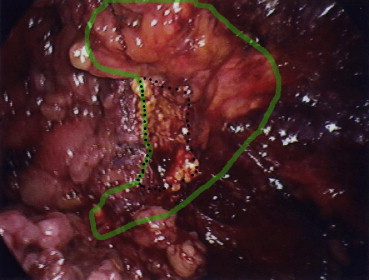

Pathological examination revealed that all adrenal tumors were removed en bloc ( Figure 1 ;  Figure 2). No peri- or postoperative complications occurred. All patients started oral intake and ambulation on the day of the operation. The early cosmetic results were excellent. The hospital stay was 1–6 days (mean, 3 days). None of the patients experienced tumor recurrence during the follow-up period. Fig. 3 shows a representative pre- and postoperative computed tomography of a single patient.

The green line indicates the margin of the adrenal gland and the broken line ...

Figure 2.

The green line indicates the margin of the adrenal gland and the broken line indicates the resection margin after partial adrenalectomy.